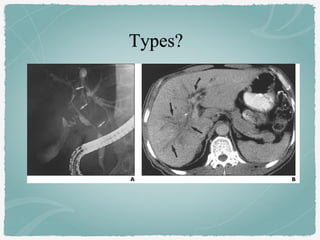

A, ERCP - diffuse narrowing (arrows) of right & left hepatic ducts &

extrahepatic duct. Complete obstruction of posterior segmental bile ducts of

right lobe.

B, CT (PV phase) - left intrahepatic bile duct dilatation (curved arrow) &

obliteration of bile ducts in right hepatic lobe & hepatic hilum.

Ill-defined, branchlike, low-attenuating mass (straight arrows) represents

Periductal infiltrating intrahepatic cholangiocarcinoma.